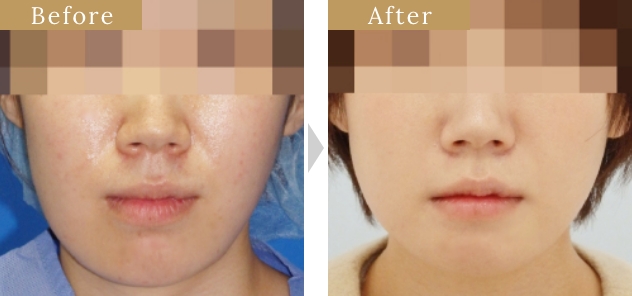

症例